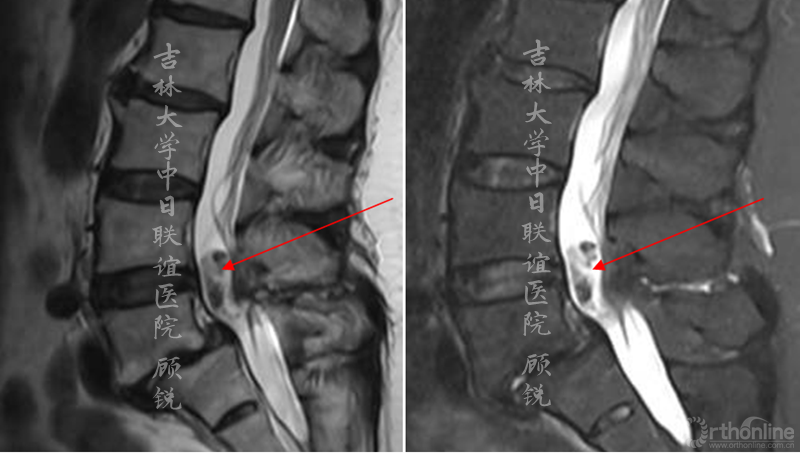

增强MRI增强如下:

腰椎增强MRI示:

占位组织强化明显为实质病变,依据瘤体与硬膜间呈锐角;T1W1:等信号;T2W1:混杂高信号STIR:环状增强,Non-enhancement area(+)。经科内会诊该患者的诊断为:峡部裂型腰椎滑脱(L5 Ⅱ度)、腰椎管内占位性病变(神经鞘瘤?)。Ozawa H, Aizawa T, Kanno H.Epidemiology of surgically treated primary spinal cord tumors in Miyagi, Japan.Neuroepidemiology. 2013;41(3-4):156-60